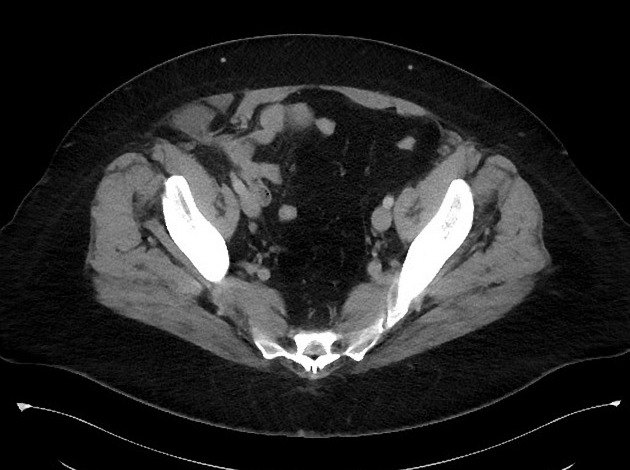

Thoát vị thành bụng

Thoát vị thành bụng - Ảnh 3

» Thông tin: Nữ giới – 50 tuổi.

» Lâm sàng: Đau hố chậu phải.